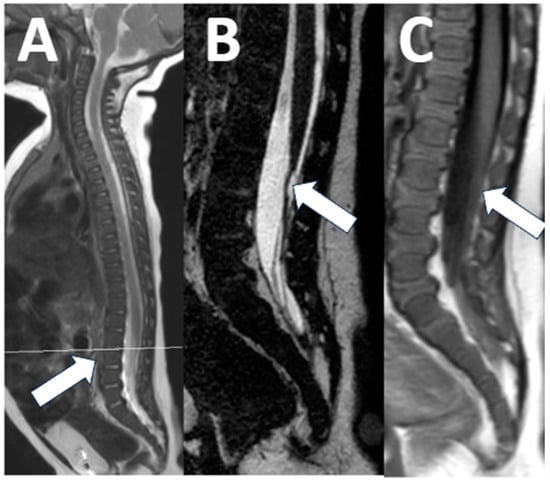

Our contextualized MRI non-accidental trauma protocol includes sagittal T2-weighted images with fat suppression to assess for the presence of ligamentous injury, intraspinal pathology, and any bone edema (Figure 9).

Figure 9. Non-accidental trauma spine imaging. (A) A 23-month-old male with suspected non-accidental trauma. The fat-suppressed sagittal T2 images show an L2 vertebral fracture with mass effect on the conus ((A), short arrow), as well as multiple levels of interspinous ligament injury at C1–6 and at L2–3 ((A), long arrows). Of note, using an inversion recover (STIR) technique for fat suppression in this case limits the evaluation of the spinal cord and spinal canal. (B) An 8-month-old male with suspected non-accidental trauma. Here, a fat-saturation technique was used, which improves the visibility of the spinal cord and identification of large intradural hematomas compressing the cauda equina ((B), short arrows). A downside of fat saturation is the inhomogeneity of the fat suppression, with areas of failed fat suppression ((B), long arrow).